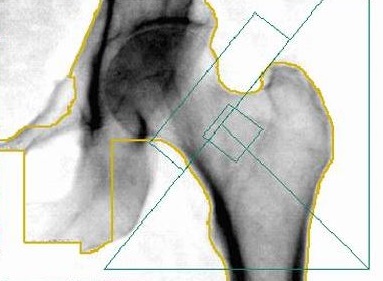

L’os absorbe les photons qui le traversent en partie. Un détecteur de photons est installé de l’autre côté de l’os. Plus l’os est dense, moins nombreux sont les photons qui atteignent le détecteur. La mesure du rayonnement après la traversée de l'os donne donc un renseignement sur sa densité. Pour obtenir une indication de l’ensemble du squelette, il suffit de mesurer deux sites seulement: l’os de la colonne et celui de la hanche. Parfois on mesure le poignet, ou même, exceptionnellement, le corps en entier.